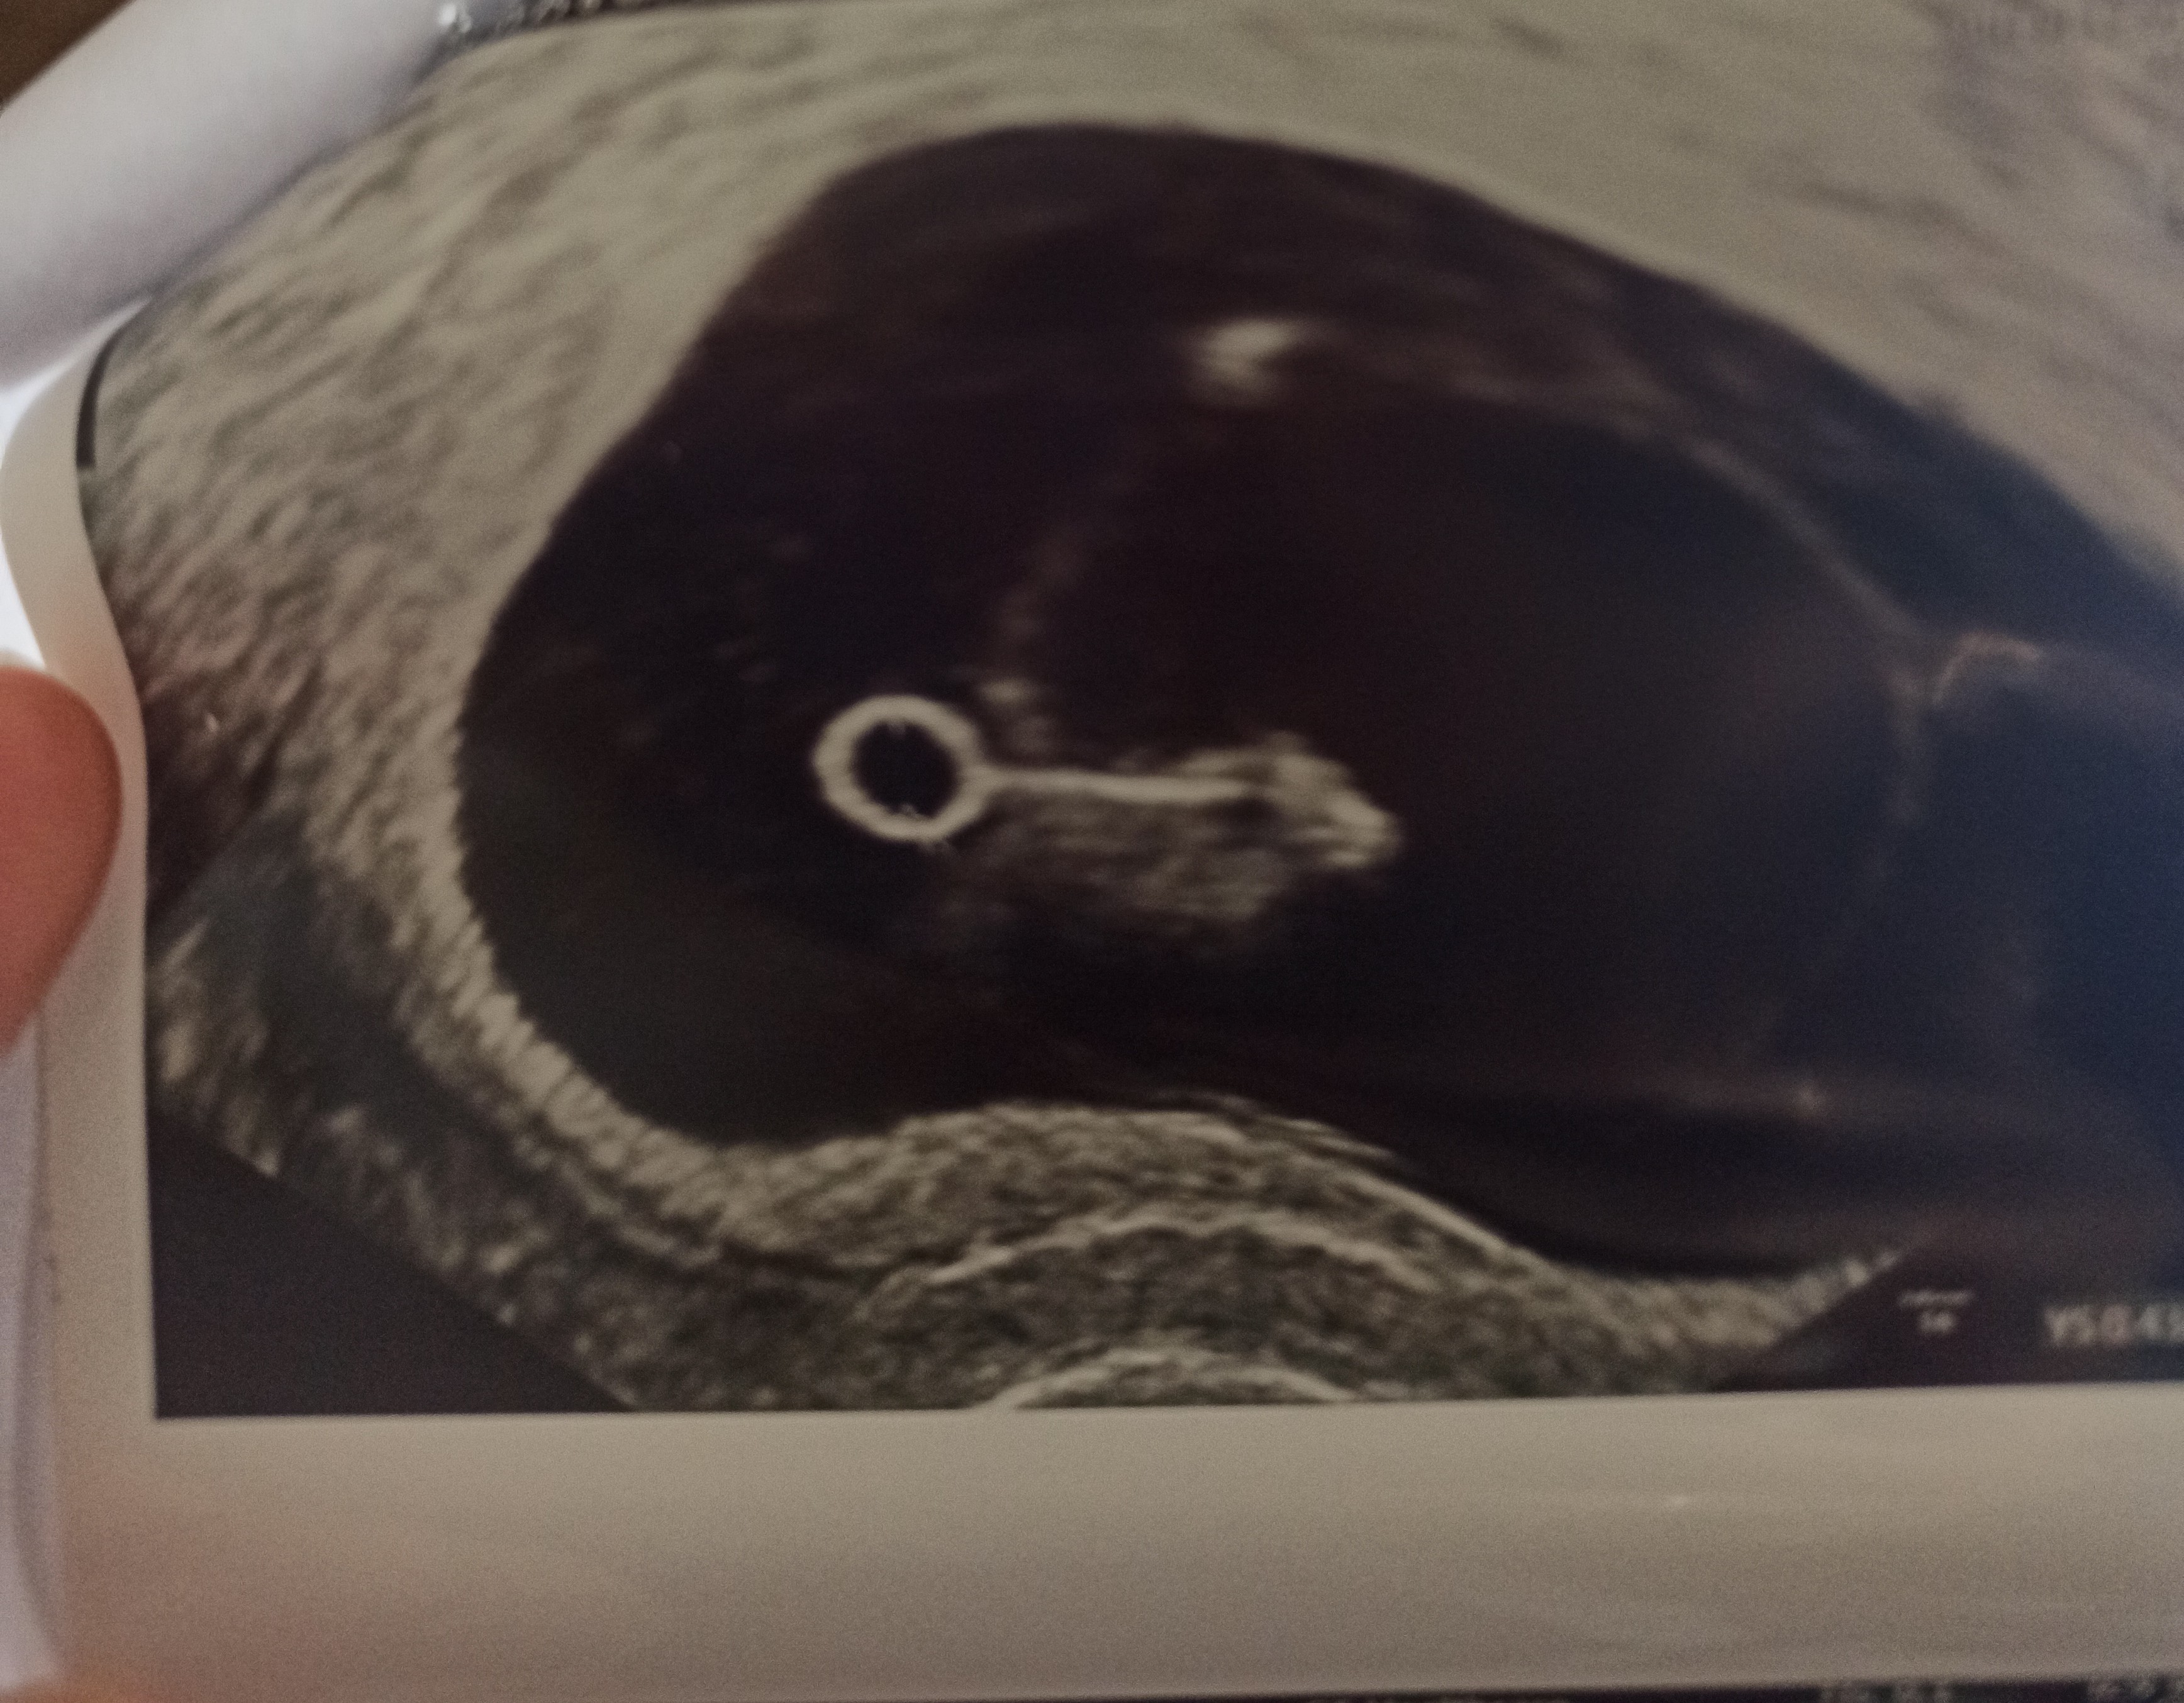

Ale mam kolejne pytanie, dostałam trzy dni żuka naszego z USG dzisiaj, ale jedno jest super dziwne 👽 wygląda jak kluczyk albo to do puszczania baniek mydlanych, co o tym sądzicie? XD

• IMG_20220525_112354.jpg

IMG_20220525_112354.jpg

1,7 MB · Wyświetleń: 130